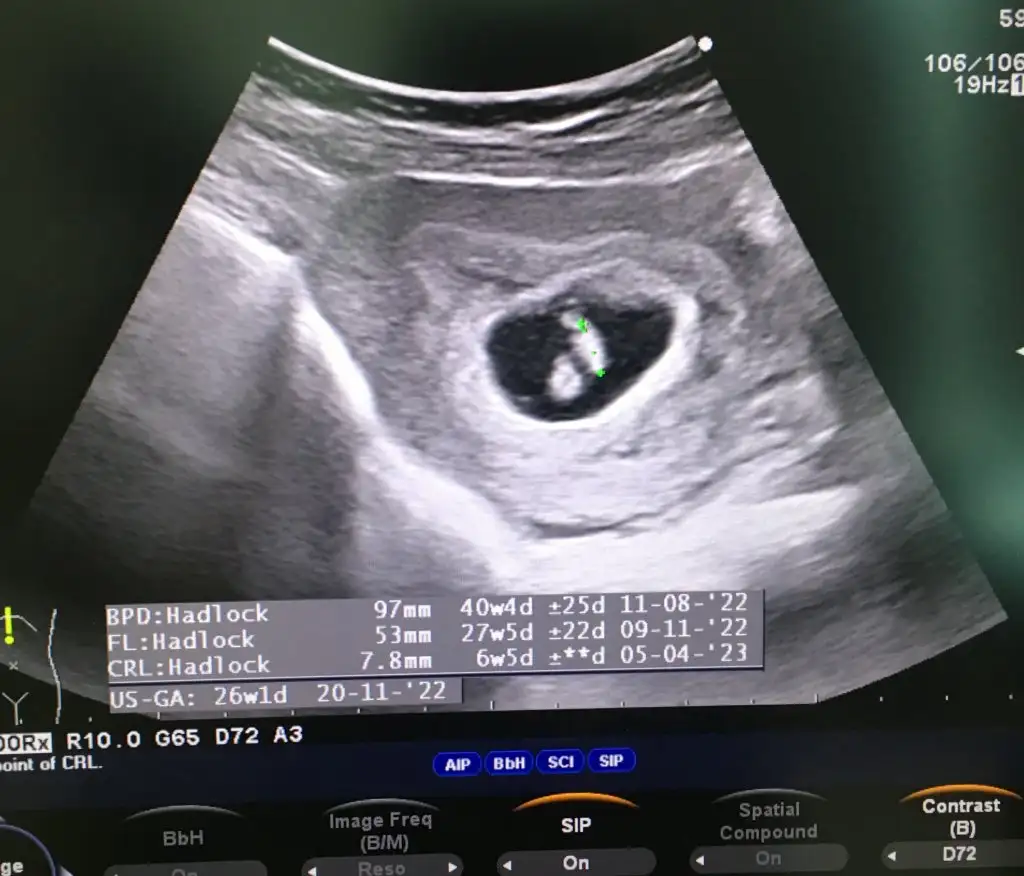

Ikinci ogluma hamileyim ikisininde kesesi yuvarlakti bu teoriyi çürütüyor

Zaten sağ kız sol erkek karından baktı iseOğlumun kese muz şeklindeydi.Bunda da kesesi aynı şekilde.Tek fark biri sağda biri solda.Ama bu kiz.Bende pek tutmadı.

Yok onu biliyorum zaten.Ama kesenin şeklinin bi önemi yok.Bende kiz da oğlan da kese muz şeklinde uzun.Zaten sağ kız sol erkek karından baktı ise

Valla benim için herkes erkek demişti sivriymiş baya kız olmuşum çokta şaaapmayın sağlıklılı olsun yeterKızlar bı arkadaş keseye göre tahmin yapıyor ve hep tutuyormuş iki oğlunu da bu şekilde cok yeniyken bile tahmin etmiş...ogullarinda kesesi hep uzunmuş muz gibi...yuvarlak ve yuvarlağa yakın olanlar hep kızdır diyor..ve bayağı emin konusuyor..benimki şişman bı fasulye gibi oo kesin kız görürsün dedi...sizlerin keselerinin şekli nasıldı ve cinsiyet neydi konusalimmi![]()

Benim ultrasonumuda yorumlarmısınız rica etsemBu bir kiz bebek.